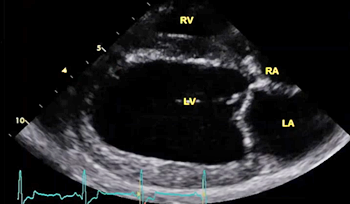

The echocardiograph examination shows the dimensions of the heart chambers, wall thickness and movement, valve movement and lesions, fractional shortening, among other characteristics. The echo screen shows the amount of wall contraction, which enables the operator to determine contractility, preload*, and afterload*. These factors are used to calculate "fractional shortening" (FS%) which is used as an indication of ventricular performance and of myocardial contractility.

* Preload is the blood filling the left ventricle, thereby stretching the heart muscle cells before contraction. Afterload is the blood contained in the left ventricle against which the heart contracts to eject that blood into the arteries.

(In the image at right, the red spurt of blood is shooting upward and backward, from the left ventricle, through the not-fully-closed mitral valve, back into the left atrium.)

The more severe the MR, the greater likelihood the MVD will progress more rapidly. The severity of MR is calculated as a percentage, using echocardiography, particularly color flow Doppler. MR is classified as:

• No MR (0%)

• Mild MR (under 20%)

• Moderate MR (20% to 50%)

• Severe MR (over 50%)